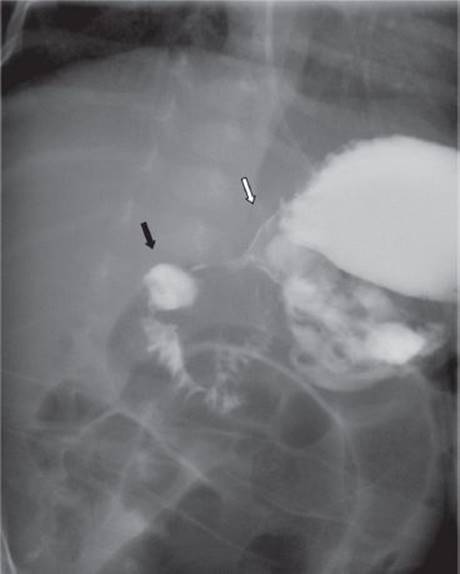

The clinical history and the physical exam alone are sufficient to make a diagnosis of pyloric stenosis in the majority of infants with the condition. Electrolytes and an abdominal ultrasound (Figure 1) confirm the diagnosis and evaluate the severity of the associated electrolyte imbalance. Ultrasound is very sensitive and specific for the diagnosis of pyloric stenosis. It is quick, available, inexpensive, noninvasive, and does not expose the child to radiation. A pylorus is considered hypertrophied if the thickness is ≥4 mm and if the pyloric channel length is ≥16 mm. In addition to these static measurements, the radiologist can often assess whether fluid is able to pass from the stomach into the duodenum. In the uncommon situation that the diagnosis is not clear after physical exam and ultrasound, an upper gastrointestinal series can show a distended stomach that cannot empty due to pyloric obstruction (“shoulder sign”) and a narrowed pyloric channel (“string sign”) (Figure 2).

FIGURE 2 • Fluoroscopy after oral contrast. A string sign is seen between the antrum (white arrow) and the duodenal bulb (black arrow) indicating pyloric stenosis.